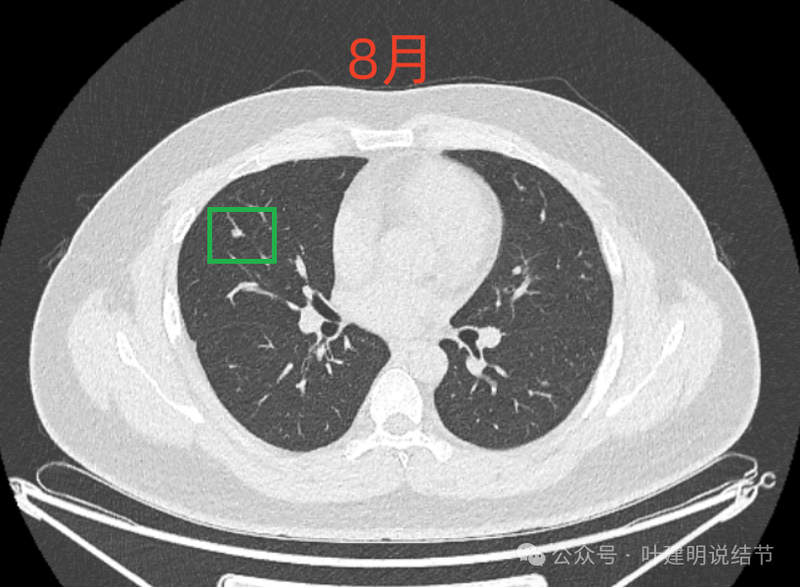

病灶4:

左下磨玻璃微小结节,轮廓与边界清楚,像是肿瘤范畴的,肺泡上皮增生或不典型增生可能性大,近期风险小。

8月时与后来的相仿。

现在的人工智能辅助诊断系统太过敏感,非常微小的结节都给你找出来,但是对于临床来说并没有多大意义。当结节才几个毫米的时候,既没有办法明确到底是什么,也没有必要明确到底是什么,按照中华医学会肺癌诊疗指南,8毫米以下纯磨玻璃结节或5毫米以下实性结节(包括混合密度结节实性成分不足5毫米)也就是年度复查就可以。所以其实并不一定要在意到底有多少处结节,或者要考虑是什么。主要就关注最主要的病灶,如果主病灶仍没有风险可以年度体检复查,那就可以随访,不能也不必有过大的思想顾虑。我看了你的CT,目前这些结节均风险小,其中右侧桔色框起来的是所谓主病灶,仍是纯磨密度,又还小,考虑不典型增生可能性较大;左下桔色的也是磨玻璃密度,但轮廓不如右上这处清楚,若确实肿瘤范畴,也是原位癌或不典型增生可能性大,但也有少许慢性炎伴肺泡上皮增生或纤维增生的可能性;中叶绿色的密度过高,更符合良性些;右下黄色的过小,11月份的像磨玻璃密度,边界较清,但对比8月时的,此灶不太明显,当然本身过小,也可能没有扫到最明显层面,不过总归风险小,能观察随访(左下的也8月时更显淡和不明显点)。总体上,这几处病灶都是风险还低,可以继续半年到一年复查随访,真若有明显进展并具有一定的风险再来干预处理不影响预后。本身年纪轻,又是多发结节,目前的病灶又都风险低,可以过于积极赶紧处理。意见供参考!